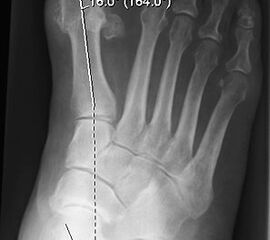

Der Talo-Metatarsale I Winkel bzw. die laterale talonaviculare Subluxation auf der stehenden dorsoplantaren Aufnahme des Fuβes dokumentieren das Ausmaβ des Vorfuβ abductus (Abb. 6 a,b). Ein dp Talo-Metatarsale I Winkel von > 10° (nach medial konvex) ist als pathologisch anzusehen. Mit der Bestimmung der talocalcanearen Divergenz (Abb. 6 c) erhält man ein Eindruck über das Ausmaβ des Rückfuβ valgus; eine leichte Divergenz bis ca. 12° gilt als physiologisch 20.

Talo-Metatarsale I Winkel >10°: Vorfuß abductus (Abb. 6a,b)

Talocalcaneare Divergenz >12°: Rückfuß valgus (Abb. 6c)